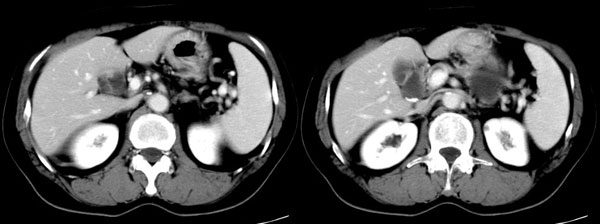

ct平扫加增强扫描:胆囊折叠,壁厚,其内见结石。胰腺体尾部见一5.8x7.5cm囊性肿物,ct值12hu,壁薄,增强扫描未明显强化,胰头不大,强化均匀。

ct诊断:1.胆囊炎,胆囊折叠并结石。

2.胰体尾部囊肿。